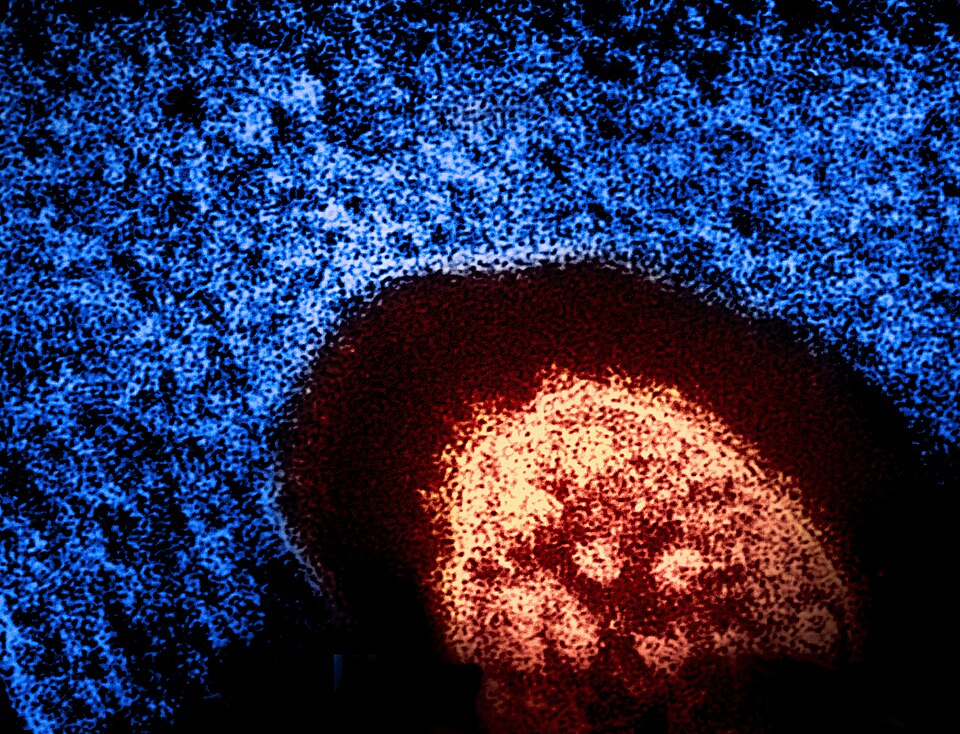

Малите сипаници се многу заразна болест предизвикана од вирус, која лесно се шири кога заразено лице дише, кашла или кива. Може да предизвика тешка болест, компликации, па дури и смрт. Од малите сипаници можат да заболат сите, но најчесто се јавува кај децата. Малите сипаници го инфицираат респираторниот тракт, а потоа се шират низ телото. Симптомите на мали сипаници обично започнуваат 10-14 дена по изложувањето на вирусот. Исипот е најкарактеристичен симптом. Раните симптоми обично траат 4-7 дена. Тие вклучуваат течење на секрет носот, кашлица, црвени и насолзени очи (конјуктивитис), мали бели дамки во внатрешноста на образите.